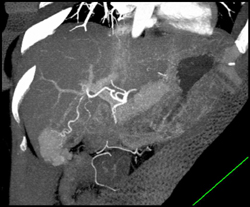

Focal Nodular Hyperplasia (FNH)